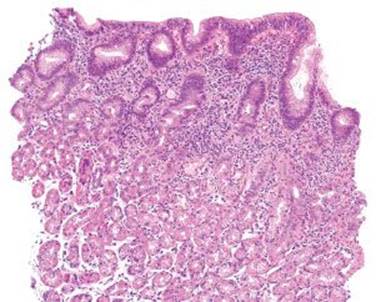

Figure 2.121 Lymphocytic gastritis pattern. The changes of lymphocytic gastritis are often prominent enough that they can be identified at scanning magnification, obviating the need for intraepithelial lymphocyte counts. The IELs usually affect the entire stomach but are more evident in the oxyntic mucosa and are more prominent in the superficial epithelium as compared to the deeper glands. Note the diffuse mixed inflammatory infiltrate in the lamina propria.